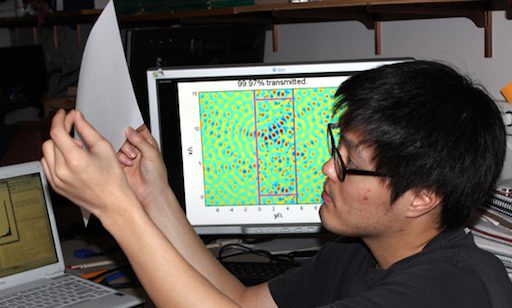

New algorithms and theory for shining light through non-transparent media

Their technique utilizes backscatter analysis to construct “perfectly transmitting” wavefronts.

Seeing through materials

By developing a fast algorithm to map out the paths light takes through yogurt, researchers aim to someday see through skin.